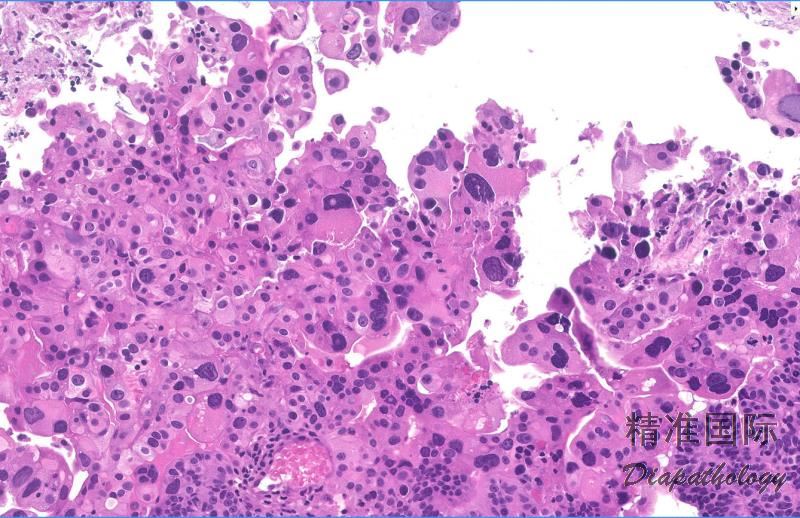

1. 由大的怪异的多形性细胞呈片状或巢状增生,细胞间黏附差;

2. 细胞可多核,也可单核,与破骨样细胞不同,大细胞呈束状排列而非均匀分布;

3. 常与子宫内样癌同时存在,也可合并其他高级别癌;

4. 间质及肿瘤内常见淋巴细胞、浆细胞、嗜酸细胞及中性粒细胞浸润;